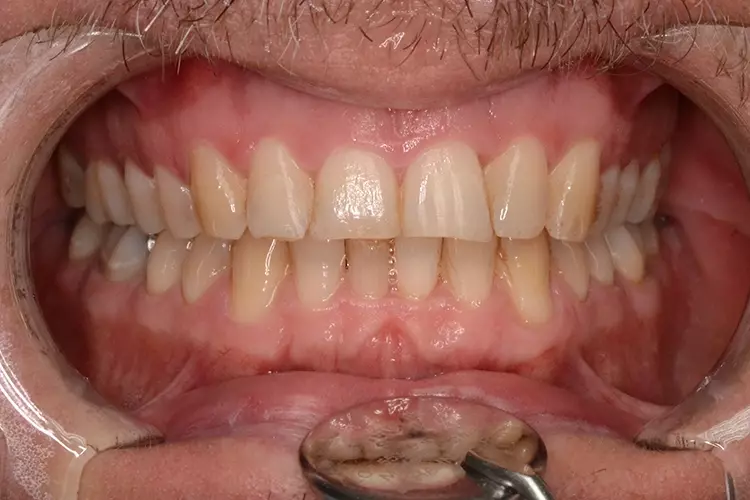

Bei dem heute 49-jährigen Patienten wurde seit Kindertagen versäumt, die Ober- und Unterkieferzahnbögen kieferorthopädisch auszurichten. Der Patient leidet seitdem stark unter seinen Zahnfehlstellungen.

Die Fraktur des stark elongierten Zahnes 21 war für den Patienten der Ausgangspunkt, sowohl die Front des Ober- als auch des Unterkiefers prothetisch überarbeiten zu lassen. Dabei wurde der frakturierte Zahn 21 durch ein navigiert eingesetztes Sofortimplantat ersetzt, während die verschachtelt stehenden Zähne 12 und 42 durch eine Brückenversorgung korrigiert wurden (Abb. 4a-j).